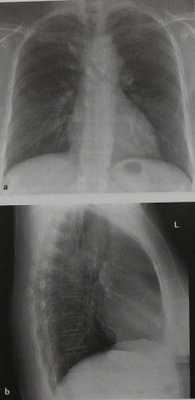

Бессимптомная мешотчатая аневризма грудной аорты у женщины 43 лет. а На обзорных рентгенограммах грудной клетки видны несколько расширенная тень дуги аорты с мелкими очагами обызвествления в стенке, обращенной к трахее, и округлое выпячивание под дисковидной проекцией дуги аорты.

b Трахея и правый главный бронх смещены. На снимке в боковой проекции верхнее средостение имеет большую, чем обычно, плотность. При расспросе больной выяснилось, что она получила травму груди.